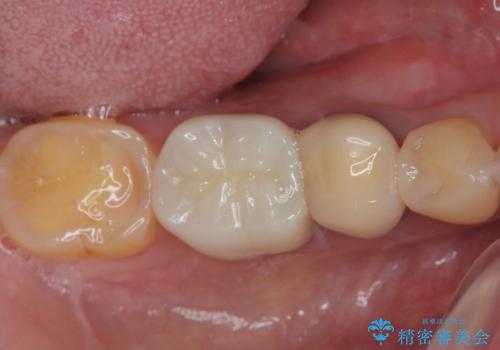

- 以前他院にて、保険診療で治療した金属のブリッジをやり替え希望の患者様です。

奥歯であっても、大きく笑うと金属色が目立ちます。

金属ブリッジを除去し、虫歯を完全に除去し、形を整え、

精度の高いシリコーン材料にて型どりをしました。

精度の高いブリッジなので、しみるなどの症状もなく経過も良好です。